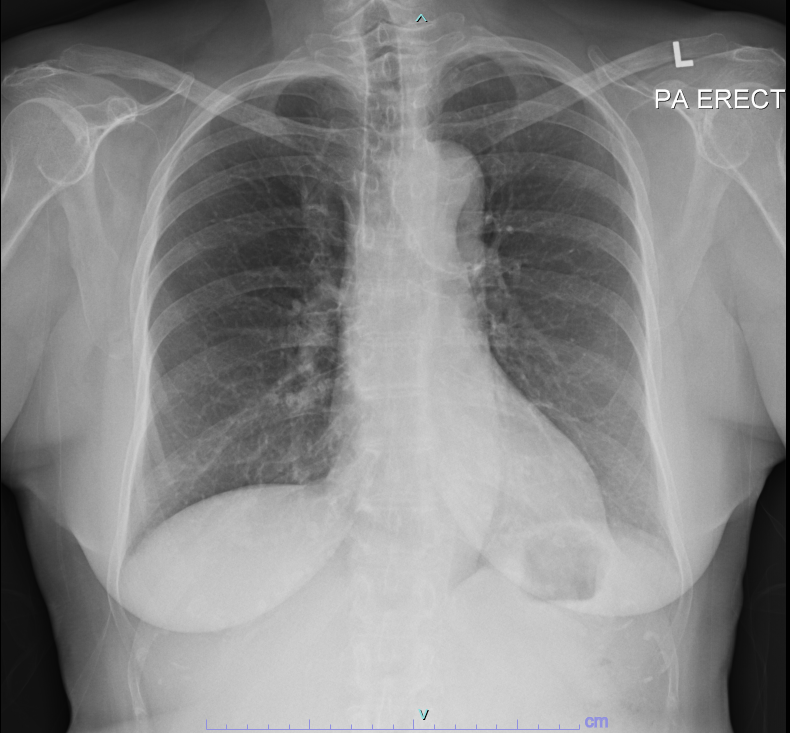

72 years old lady with background history of coronary artery disease, hypertension, dyslipidaemia, allergic rhinitis, dyspepsia presented with reduced effort tolerance for 3 months. Denies chest pain, lower limb swelling or paroxysmal nocturnal dyspnea. NYHA 2. No cardiac murmur, no crepitations, normal jugular venous pressure and no pedal edema on examination.

Relevant Test Results Prior to Catheterization

Creatinine 78 eGFR 65, TroponinT 6, proBNP 64 pg/mlEchocardiogram showed Ejection Fraction 53%, with hypokinesia mid and basal posterior, basal septal, mid and basal inferior segments.A PET-CT Cardiac showed moderate area of non-transmural infarcted myocardial segments with a small area of peri-infarcted stress induced ischaemia in the left circumflex/ right coronary artery territories. A diagnostic coronary angiography was performed in view of PET-CT Cardiac findings